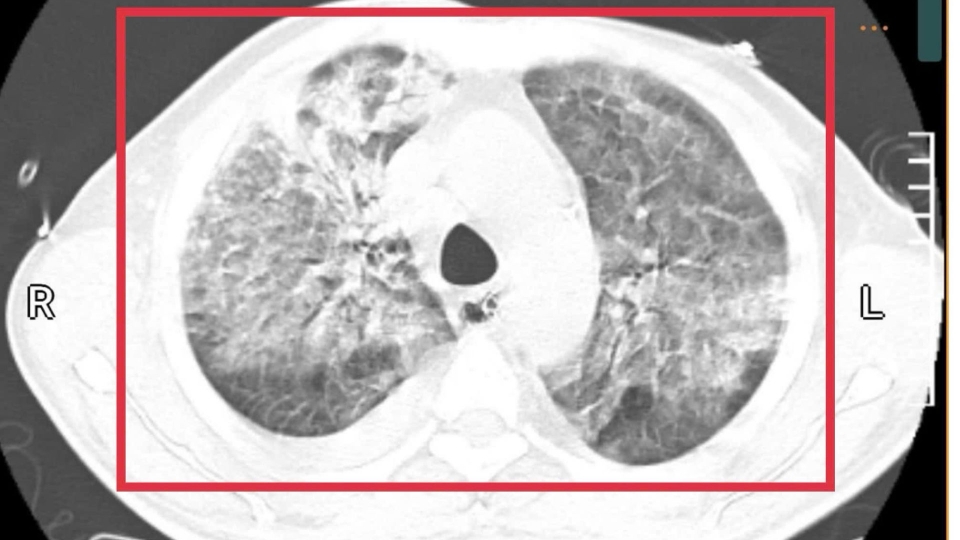

Khi tiếp nhận, bệnh nhân được thăm khám lâm sàng, làm xét nghiệm máu và các kỹ thuật chẩn đoán hình ảnh. Kết quả ghi nhận dương tính với sán lá gan lớn và giun đũa chó mèo. Đồng thời phát hiện ổ áp xe gan kích thước sấp xỉ 5 cm, kèm theo tăng chỉ số viêm và tăng bạch cầu ái toan. Theo Bác sĩ Hương: “Ổ áp xe gan khá lớn. Nếu bệnh nhân đến muộn có thể dẫn đến vỡ ổ áp xe và nhiễm khuẩn huyết”.